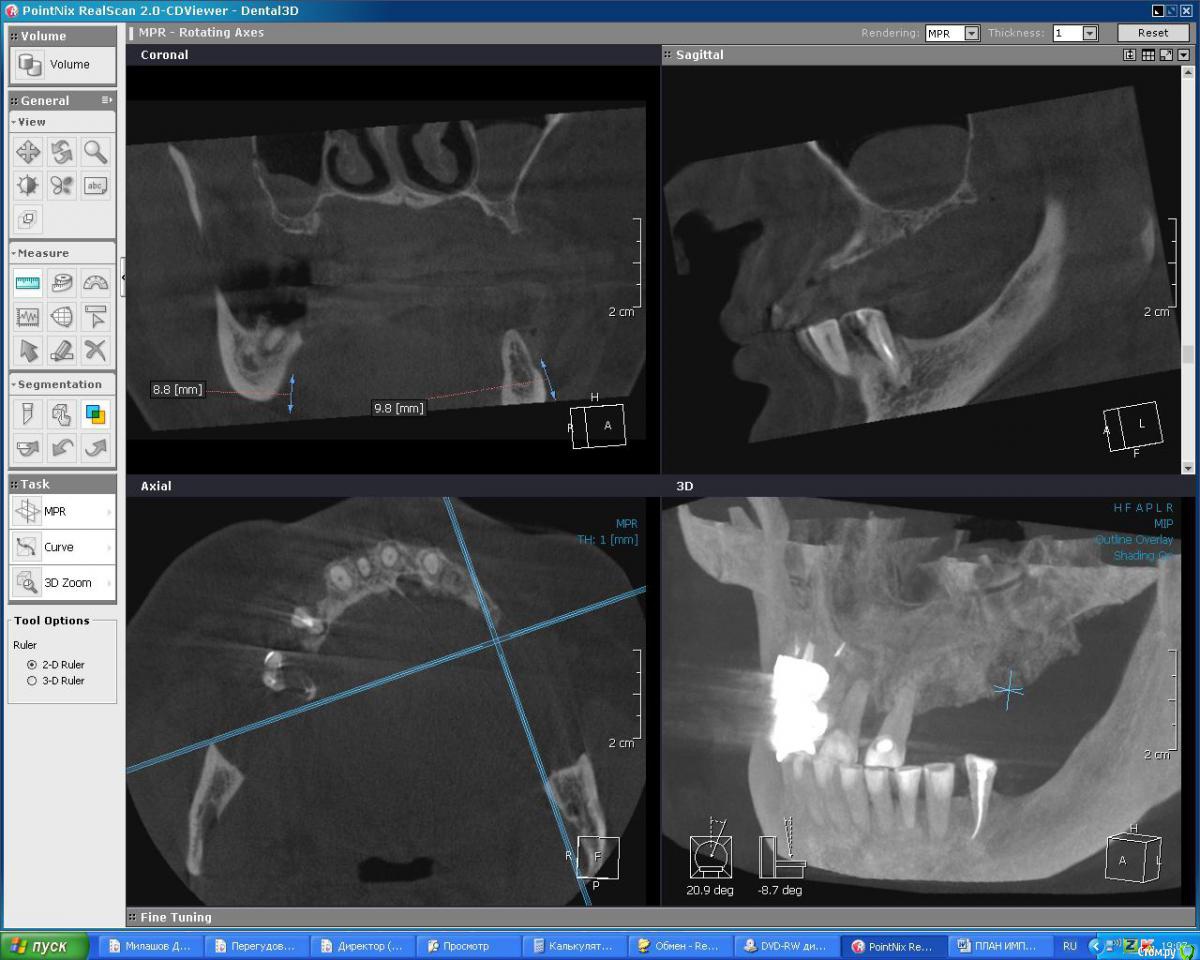

DoktorDre Опубликовано 23 декабря, 2015 Поделиться Опубликовано 23 декабря, 2015 Добрый вечер, коллеги. Хотим импланты, анализ моделей, кт показал что не хватает кости Небно. По высоте почти норм. Как вырастить там кость? Небный лоскут не тянется. Делать дизайн лоскута с щечной стророны? Ссылка на комментарий